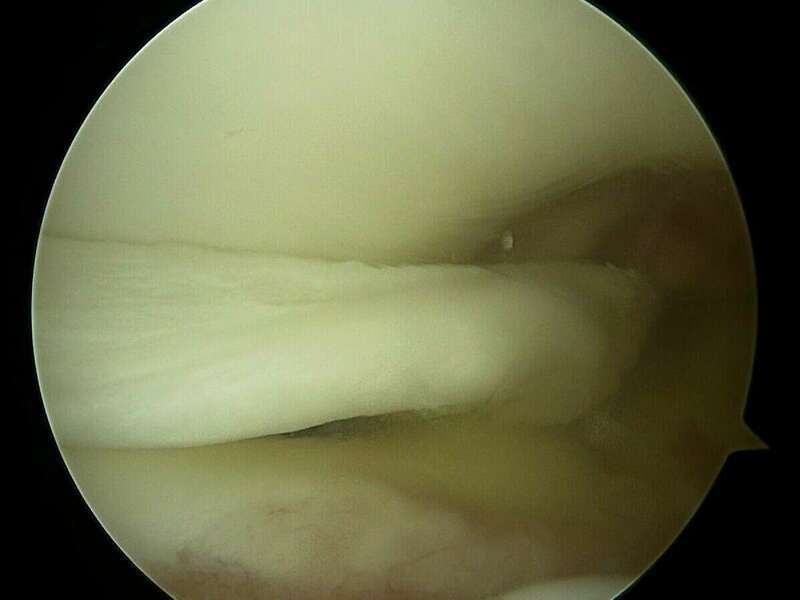

L’anse de seau méniscale est une fissure verticale qui s’étend de la corne postérieure à la corne antérieure. Cette anse est le plus souvent luxée dans l’échancrure inter-condylienne et provoque des blocages en extension.

Les douleurs sont généralement brutales et intenses avec un gonflement du genou. Le blocage en extension de votre genou correspond à une luxation méniscale dans l’échancrure inter-condylienne (espace situé entre les ligaments croisés et le condyle fémoral). On parle alors de fissure en anse de seau.

La plupart du temps, les lésions méniscales traumatiques sont traitées chirurgicalement. Deux gestes sont possibles : la réparation méniscale et la méniscectomie. Ces deux interventions sont réalisées au cours d’une arthroscopie et ont des indications spécifiques à chacune.